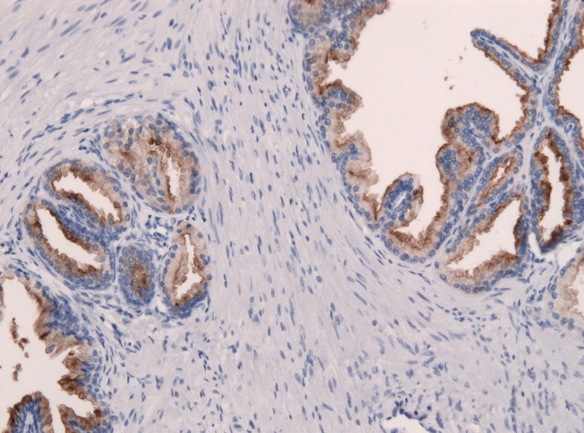

BIOPSIA PROSTATICA

Es la única prueba que logra confirmar la existencia del cáncer de próstata. Debe practicarse cuando el tacto rectal y/o el PSA están alterados, y en ocasiones es necesario repetirla.

Se realiza introduciendo una fina aguja hueca a través del recto en el interior de la próstata, para extraer muestras de tejido.

Hoy día esta prueba es molesta pero no dolorosa, gracias a la mejora de las técnicas de anestesia. Es indispensable emplear un ecógrafo con sonda endorectal para infiltrar la anestesia en la zona adecuada y guiar la aguja de biopsia con precisión. Además utilizamos un instrumento especial que realiza punciones ultrarrápidas en fracciones de segundo, mucho mejor toleradas, y que permite tomar más de 10 muestras con sencillez.